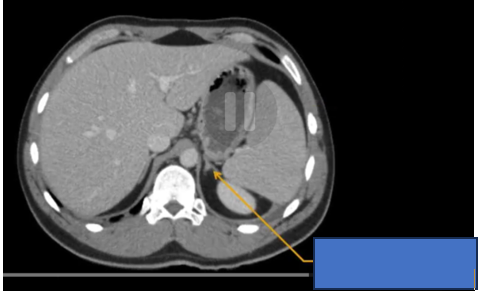

cq trong hình ?